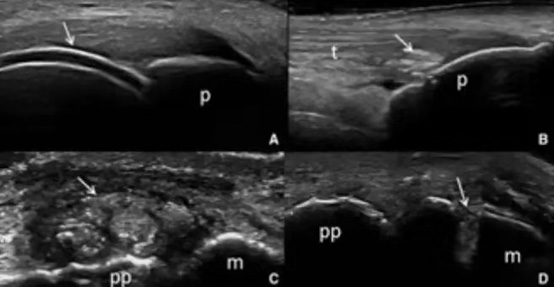

晶體相關(guān)關(guān)節(jié)炎:超聲可檢測出在關(guān)節(jié)和關(guān)節(jié)周圍結(jié)構(gòu)中沉積的尿酸鈉和焦磷酸鈣脫水晶體。可用于痛風(fēng)和焦磷酸鈣脫水晶體沉積病的診斷、以及與其他關(guān)節(jié)炎的鑒別診斷。2015年美國風(fēng)濕病學(xué)會(huì)(ACR)和歐洲抗風(fēng)濕病聯(lián)盟(EULAR)共同提出最新的痛風(fēng)分類標(biāo)準(zhǔn),包括影像學(xué)檢查如超聲證實(shí)雙邊征或雙源CT(DECT)證實(shí)有尿酸鹽沉積。雙邊征、痛風(fēng)石、聚集征、骨侵蝕等超聲表現(xiàn)可以發(fā)現(xiàn)早期痛風(fēng),評(píng)估藥物治療效果,超聲彈性成像、超聲造影(CEUS)、三維超聲等技術(shù)于肌肉骨骼領(lǐng)域的應(yīng)用,有望對(duì)評(píng)估炎癥活動(dòng)性、鑒別診斷及檢出微小病變發(fā)揮更大作用。

圖A 雙軌征 圖B 滑囊內(nèi)尿酸鹽沉積

圖C 痛風(fēng)石 圖D 骨質(zhì)破壞